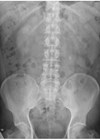

Case 1 What does this plain X-ray of kidneys, ureters and bladder (KUB) show? What, according to the 2009 The National Institute for Health and Care Excellence (NICE) guidelines, is the most appropriate first-line treatment? What factors do the NICE...